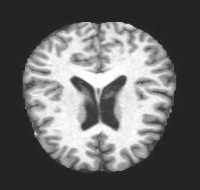

MRI Brain Scans Dataset - All Categories

Very Mild (MCI)

Early cognitive decline

Real MRI scans showing progressive structural brain changes across all dementia stages

- • Total Images: 6,400+ brain scans

- • Normal Cognition: 3,200 cases

- • Very Mild Dementia: 2,240 cases

- • Mild Dementia: 896 cases

- • Moderate Dementia: 64 cases